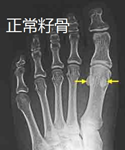

脚籽骨突出图片,足籽骨位置

工作中有意思的—足部副骨与籽骨

12种常见足踝部籽骨,小骨及变异

足籽骨位置

足部籽骨

拇指籽骨

脚大拇指籽骨图片

足籽骨的位置图

足部籽骨图片